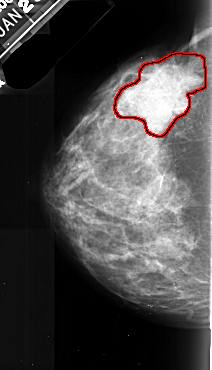

A_1027_1.LEFT_CC

LEFT_CC LINES 4801 PIXELS_PER_LINE 2746 BITS_PER_PIXEL 16 RESOLUTION 42 OVERLAY

FILE: A_1027_1.LEFT_CC.OVERLAY

TOTAL_ABNORMALITIES 1

ABNORMALITY 1

LESION_TYPE MASS SHAPE LOBULATED MARGINS SPICULATED

ASSESSMENT 5

SUBTLETY 4

PATHOLOGY MALIGNANT

TOTAL_OUTLINES 1

BOUNDARY